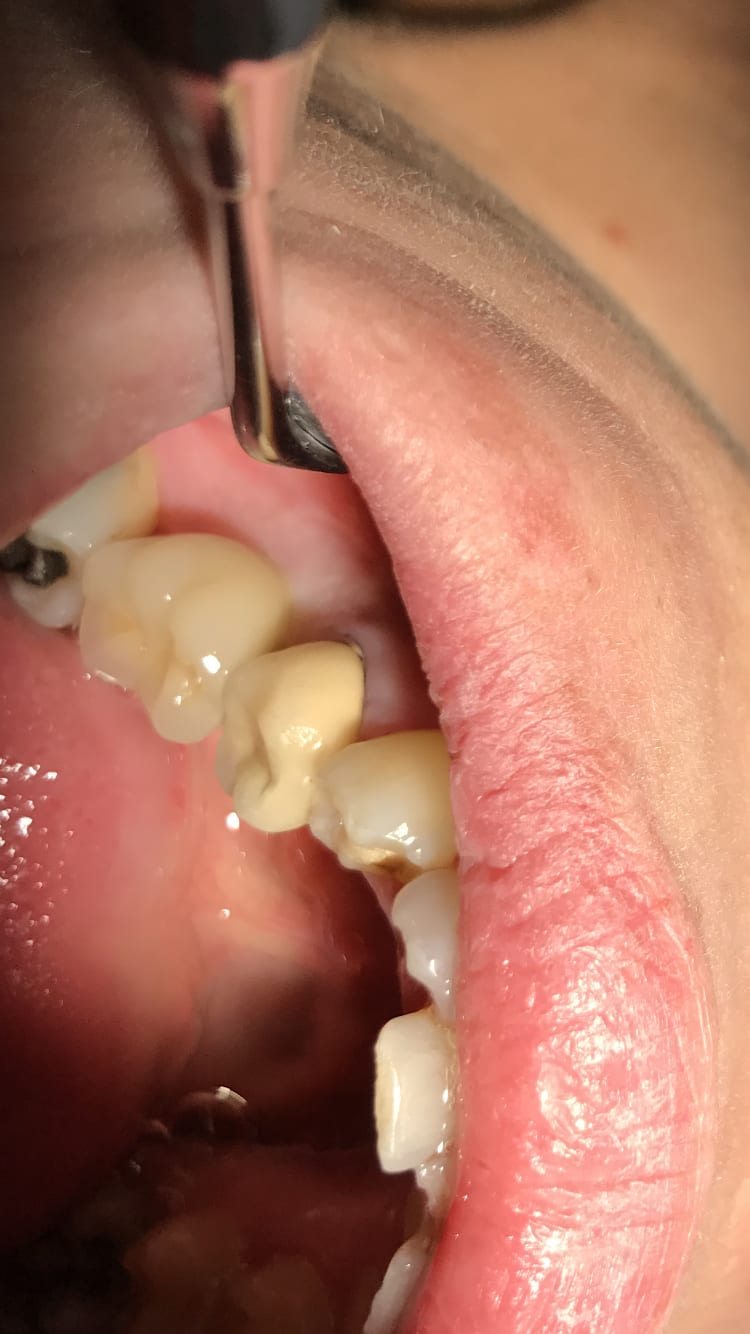

Ah oui c’est pas con ça empêche le sang de remonter ton truc ou ça empêche le fluide gingival de remonter . Ça fait comme un joint. Tiens gros overlay en compo sur 36